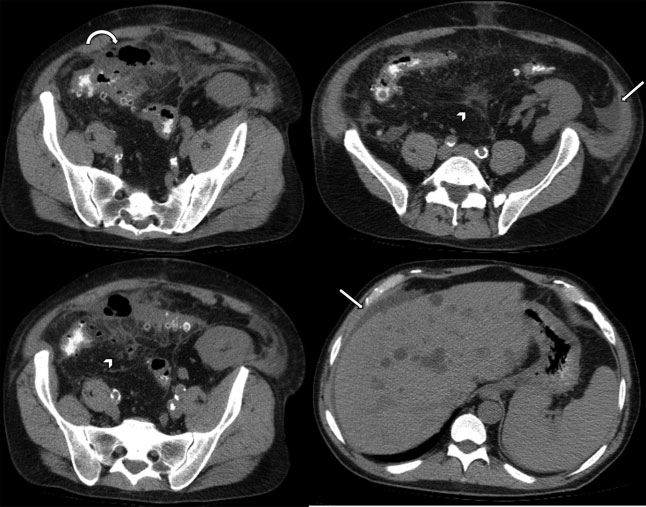

Estadio IIB: Aire distante (>5 cm del segmento intestinal inflamado). Si el paciente está estable sin comorbilidades se recomienda tratamiento conservador con eventual drenaje percutáneo guiado por imágenes; en caso contrario, resección quirúrgica con o sin anastomosis (►Fig. 7).

Estadio III: Presencia de líquido libre difuso sin evidencia de neumoperitoneo. Si el paciente está estable sin comorbilidades, se recomienda el lavado laparoscópico y drenaje; en caso contrario, resección quirúrgica con o sin anastomosis (►Fig. 8).

Estadio IV: Presencia de líquido libre difuso asociado a neumoperitoneo. Se recomienda resección quirúrgica con o sin anastomosis (►Fig. 9).